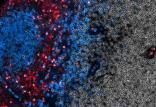

محققان دانشگاه بوستون با همکاری آکادمی علوم چین، یک شیوه جدید تصویربرداری شیمیایی با استفاده از نور مادون قرمز را توسعه دادند که امکان مطالعه دقیق با

[ادامه]